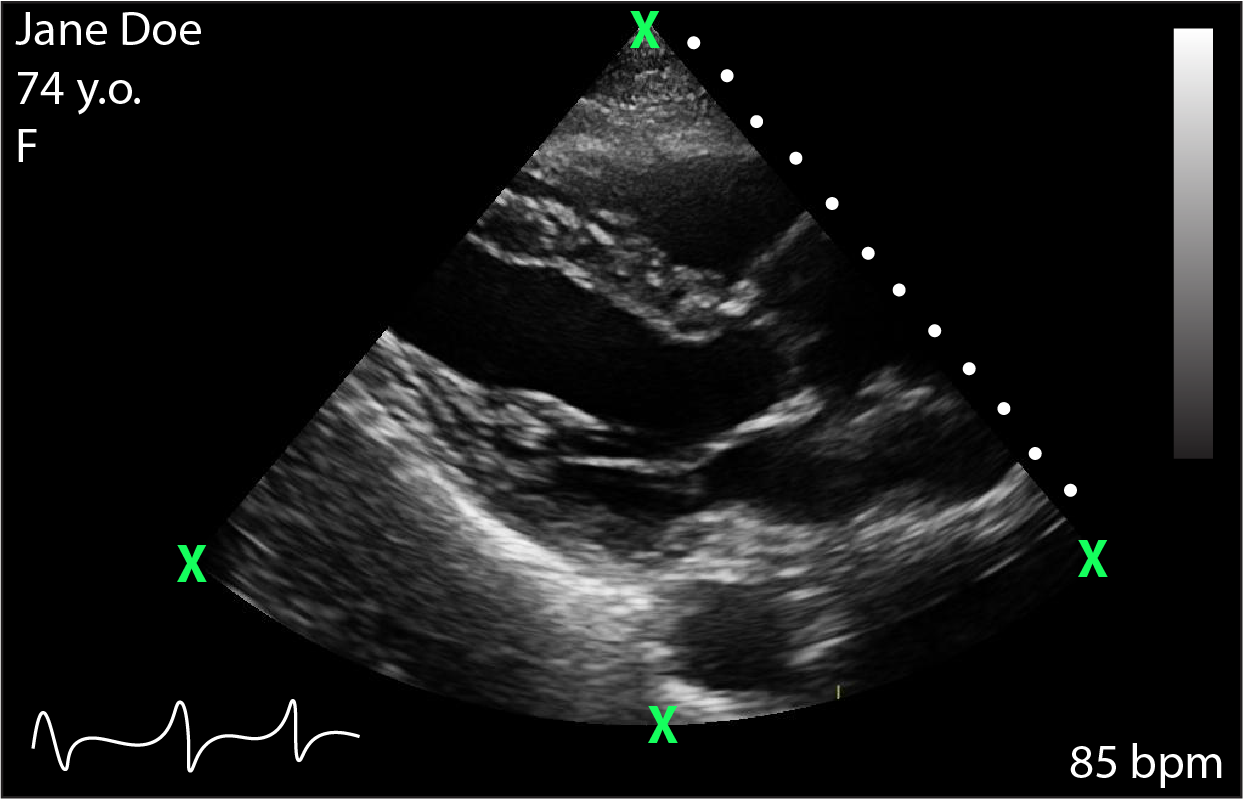

Following classic image processing techniques, further geometric assessments are made based to determine the best complete ROI to capture. Three points on the previously established ROI are used to complete this task. These three points represent either points on the circumference of the circle (Figure 3a and 3b) or points along the lower portion of a rectangular ROI (Fig. 3c), denoted with a green X𝑋X. The slope between these points is calculated. It is this first step that allows determination of a rectangular or circular ROI, as the expected slope in a rectangular ROI will be approximately 0. The midpoints of the established chords (in the case of a circle) are calculated, and the negative reciprocal of the slope is used to determine the perpendicular slope of the line (Eq. 5). Where these two perpendicular lines (dashed orange) in Figure 3 intersect will present the center C𝐶C of the circle. Again, non-convergence of the perpendiculars or non-convergence within a specified space suggests that the probe type is linear, and therefore the ROI is rectangular in nature. This can be seen in Fig. 3. Knowing C𝐶C, we can determine the radius r𝑟r of the circle of where the radius is the argmax of the radius calculated for each of the 3 original points X𝑋X to preserve a maximal ROI. The angle θ𝜃\theta subtended by the left and right-most radii is calculated (Eq. 6) to create a pie-shaped wedge mask. Of note, equation 6 will always find the acute angle. To differentiate structures seen in Figure 3a and 3b, we can exploit that in 3a, C𝐶C is well approximated near or within the pre-specified ROI, otherwise a secondary circle is calculated using available information. The secondary circle with radius r2subscript𝑟2r_{2} is used to create the notch seen at the top of the wedge in Figure 3b.

Refer to caption

Figure 3: Geometric shape determination. a) pie-shaped wedge (phased array probe) b) notched wedge (curvilinear probe) c) rectangular (linear probe)

To ascertain the efficacy of our algorithm, we had an expert user (an experienced cardiologist with expertise in cardiac ultrasound) perform manual segmentation on a randomly selected subsample of n=50 from the aforementioned NUECL echocardiography repository. Dice coefficients were calculated (Eq. 6) to ascertain the degree of intersection between image sets relative to the total area identified by each procedure alone [26]. Our domain expert identified the ROI by interacting with each image and clicking on boundary points, as seen in Figure 4. A manual review was also performed on 200 different randomly selected echocardiograms, checking outcomes from the software to ensure no patient related data leaked through.

Figure 4: Boundary detection of ROI as defined by user expert